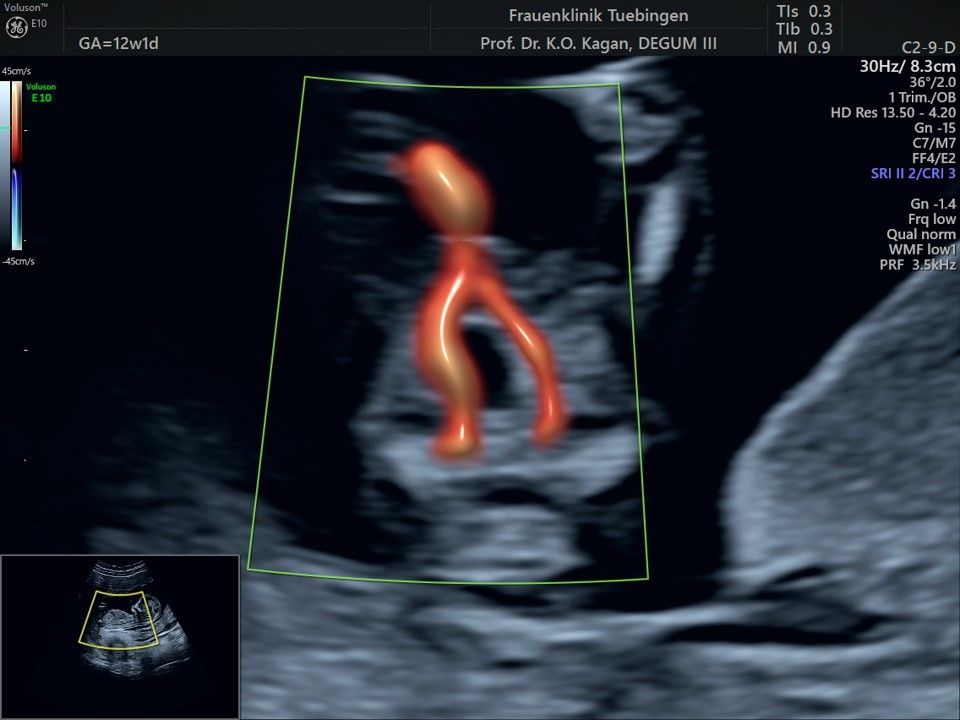

Herz